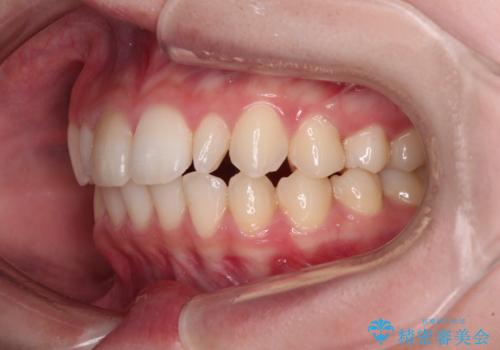

- 歯列のデコボコを気にして来院された患者様です。

安価に速やかに治療をしたいとのことで、メタルワイヤーにより矯正治療を行うこととしました。

上顎左右側切歯は矮小歯であり、矯正治療開始前にオールセラミッククラウンによる形態修正を兼ねた補綴治療を提案しましたが、特に気にならないとのことで、歯冠形態はそのままとしました。